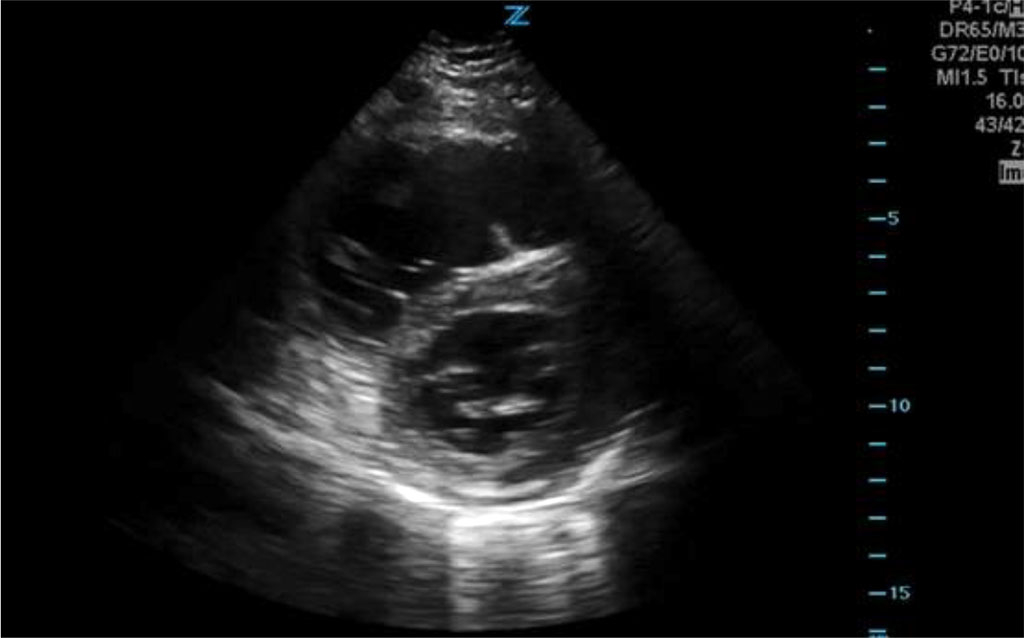

Based on the clinical picture, pulmonary embolism was suspected. An urgent cardiology consultation was called. Echocardiography in the transthoracic projection confirmed the features of massive overload of the right ventricle and the image of an empty left ventricle.

Fig.1 Echocardiographic image showing right ventricular overload